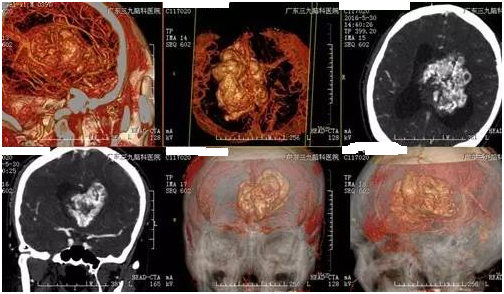

陈男子,39岁,3个月前开始头晕头痛,在卫生院抓药吃后有所缓解,近1个月症状加重伴恶心、呕吐、肢体乏力,为求进一步治疗来我院就诊。入院后完善相关检查,提示:肿瘤位于脑室内,钙化明显,形态不规则,肿瘤最大径8.1cm,双脑室不同程度扩大,诊断:双侧侧脑室巨大占位性病变;梗阻性脑积水。由神经外一科张良教授主刀切除脑室内肿瘤,解除脑积水,经系统康复治疗后,患者症状缓解出院。术后病理提示中枢神经细胞瘤,WHO II级。

▲术前CTA